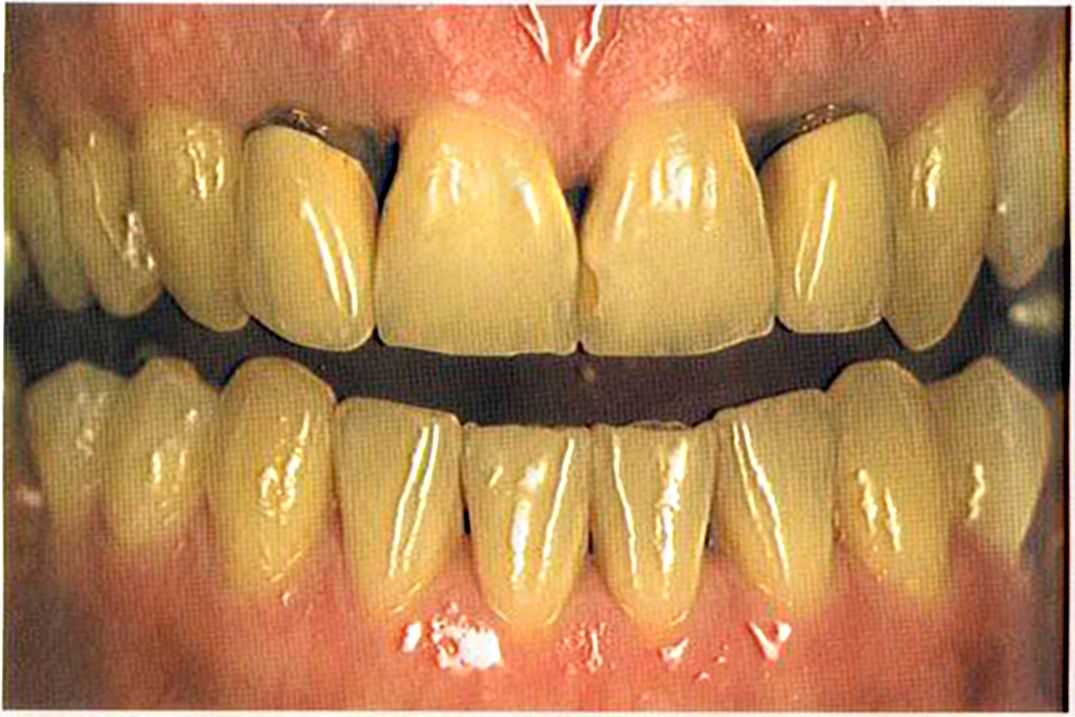

Первое лечение проходию много лет назад у другого доктора. Со временем ос те пи / ка уху дин ьась, особенно в пришеечной области. Этот пациент хотел новые коронки в области 12 и 22, по сомневсься, нас кол ько хорошо они будут выглядеть.

Результат с использованием In-Ceram развеял все сомнения, и решение об изготовлении коронки на другой боковой резец не заставило себя долго ждать.

После того как мы определит цвет зуба, решено быо сначсьа изготовить одну коронку.